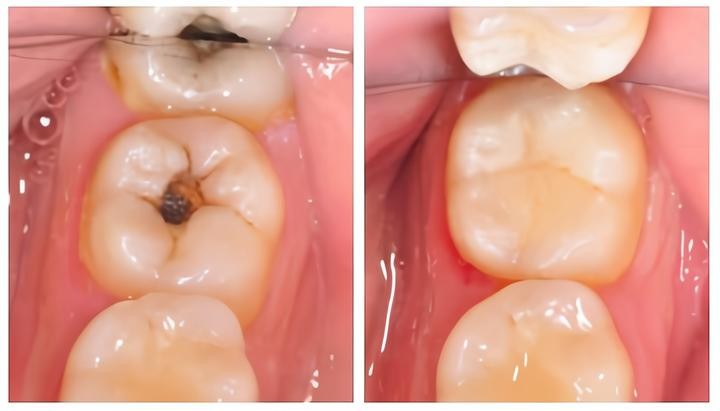

2、龋齿

当牙齿遭受致龋菌侵蚀的时候,一般初期会出现脱矿,牙齿局部发白,尔后随着时间推移渐渐变成黑点、黑线。

当发现牙齿已经存在明显的黑点黑线,可以及时到正规的口腔医院检查,如果确认龋坏的话,根据医生建议及时进行补牙修复。